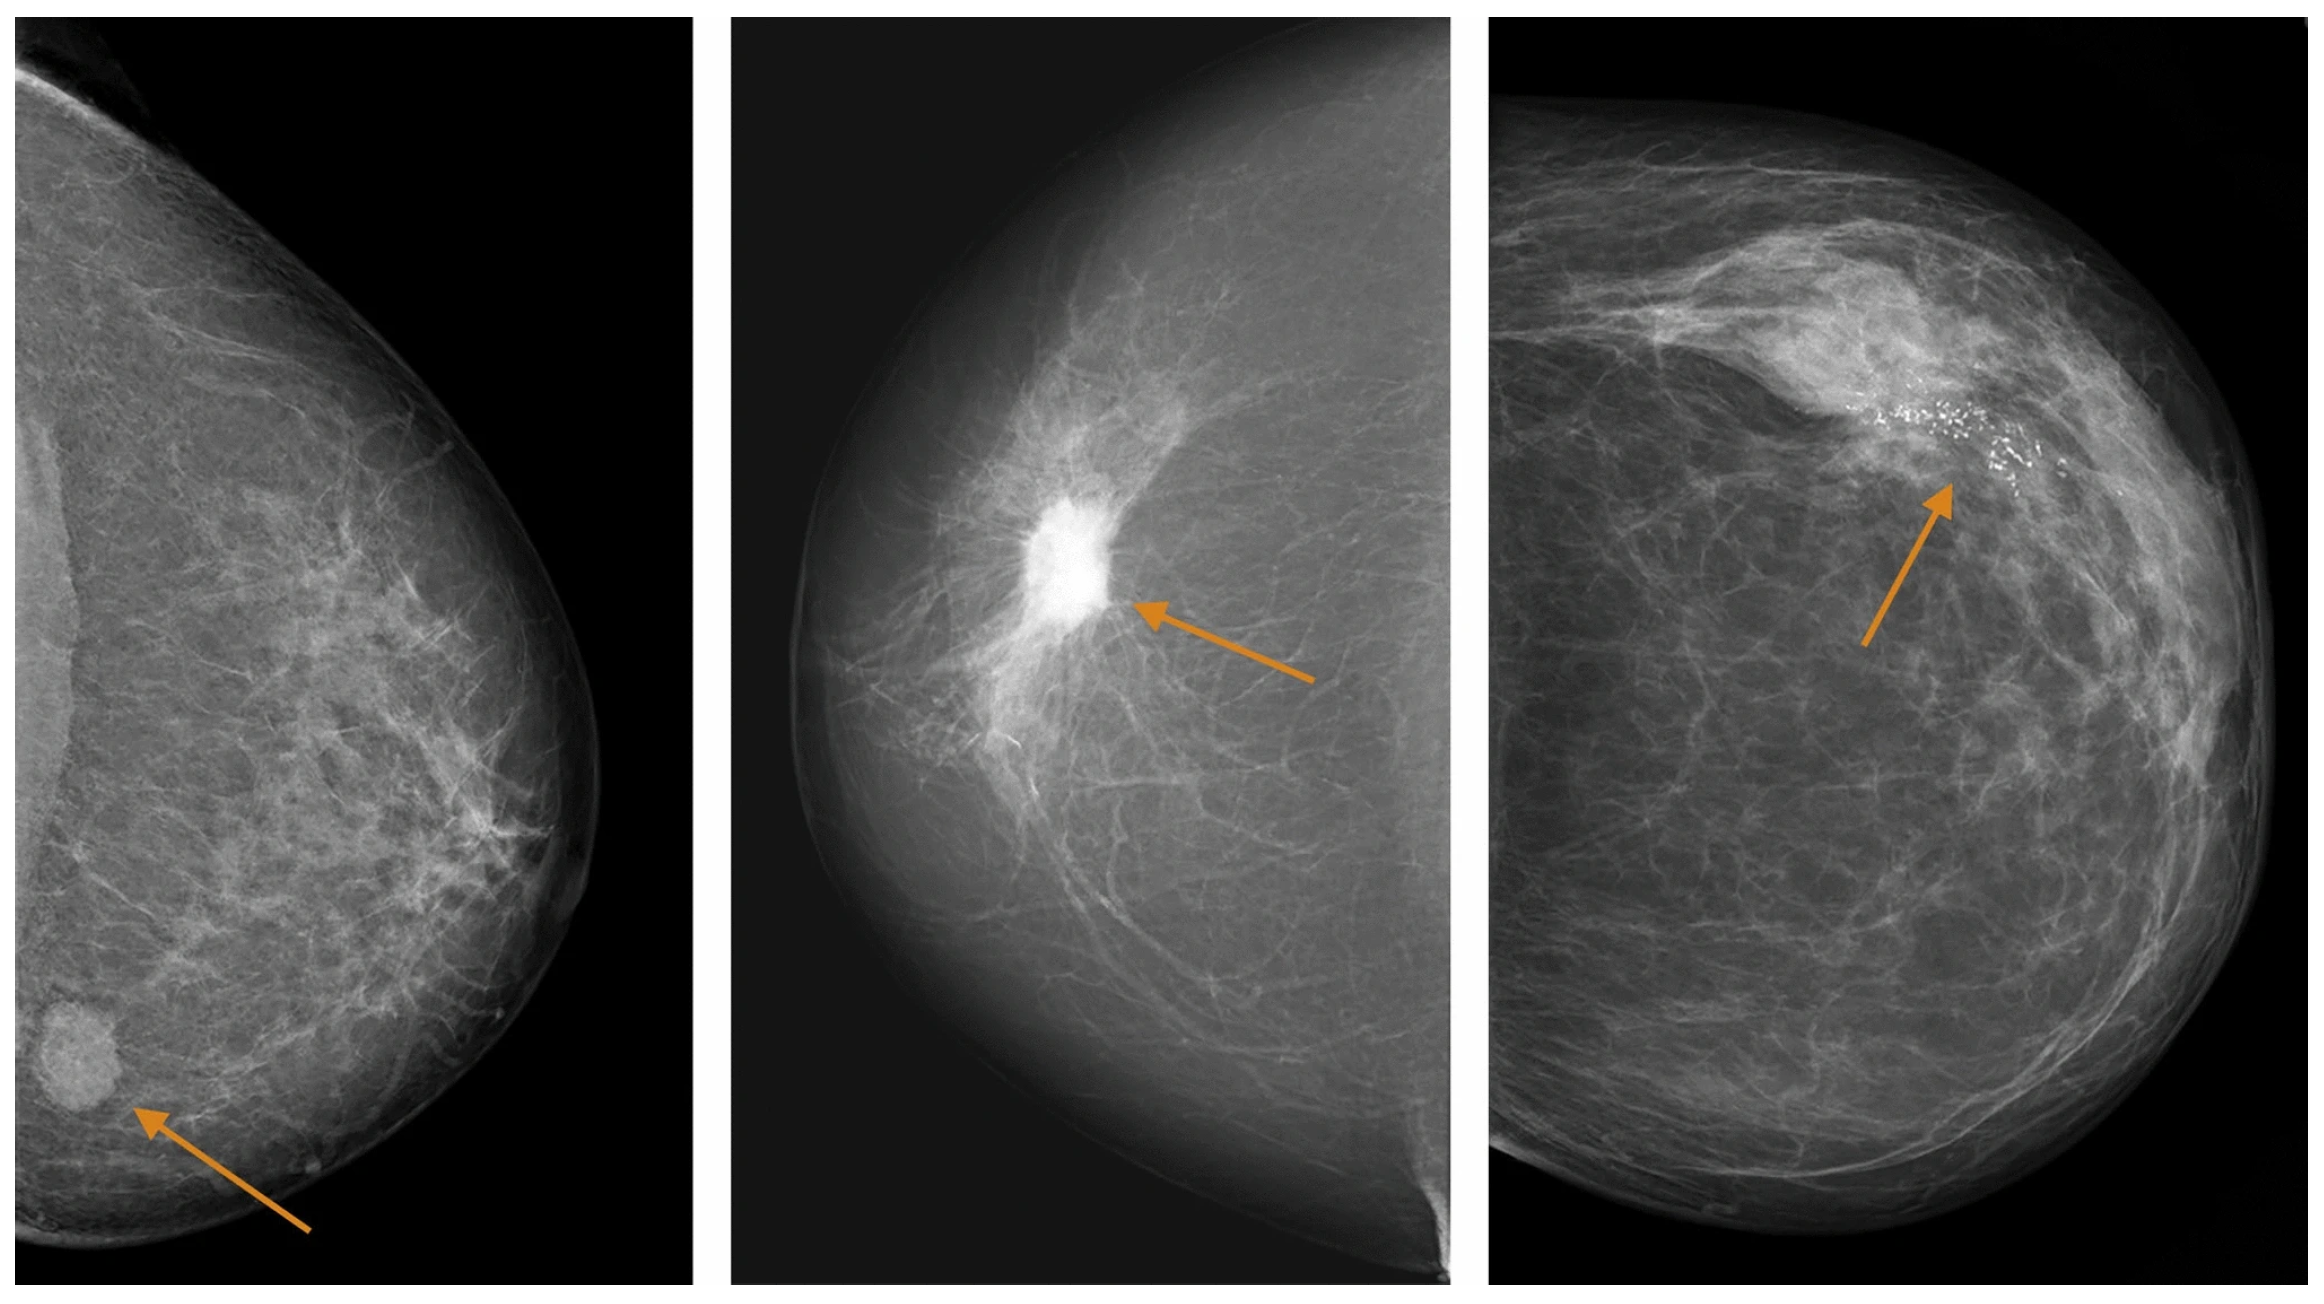

2.3. Mammography

- Sickles, E. Mammographic features of “early” breast cancer. Am. J. Roentgenol. 1984, 143, 461–464. [Google Scholar] [CrossRef]

- Gajdos, C.; Tartter, P.I.; Bleiweiss, I.J.; Hermann, G.; De Csepel, J.; Estabrook, A.; Rademaker, A.W. Mammographic appearance of nonpalpable breast cancer reflects pathologic characteristics. Ann. Surg. 2002, 235, 246–251. [Google Scholar] [CrossRef] [PubMed]

- Leibman, A.J.; Lewis, M.; Kruse, B. Tubular carcinoma of the breast: Mammographic appearance. Am. J. Roentgenol. 1993, 160, 263–265. [Google Scholar] [CrossRef][Green Version]

- Sturesdotter, L.; Sandsveden, M.; Johnson, K.; Larsson, A.M.; Zackrisson, S.; Sartor, H. Mammographic tumour appearance is related to clinicopathological factors and surrogate molecular breast cancer subtype. Sci. Rep. 2020, 10, 20814. [Google Scholar] [CrossRef]

- Niknejad, M.T. Breast Mass (BI-RADS 5). Case Study. Radiopaedia.org, 20 November 2021. Available online: https://radiopaedia.org/cases/94040 (accessed on 9 February 2026).